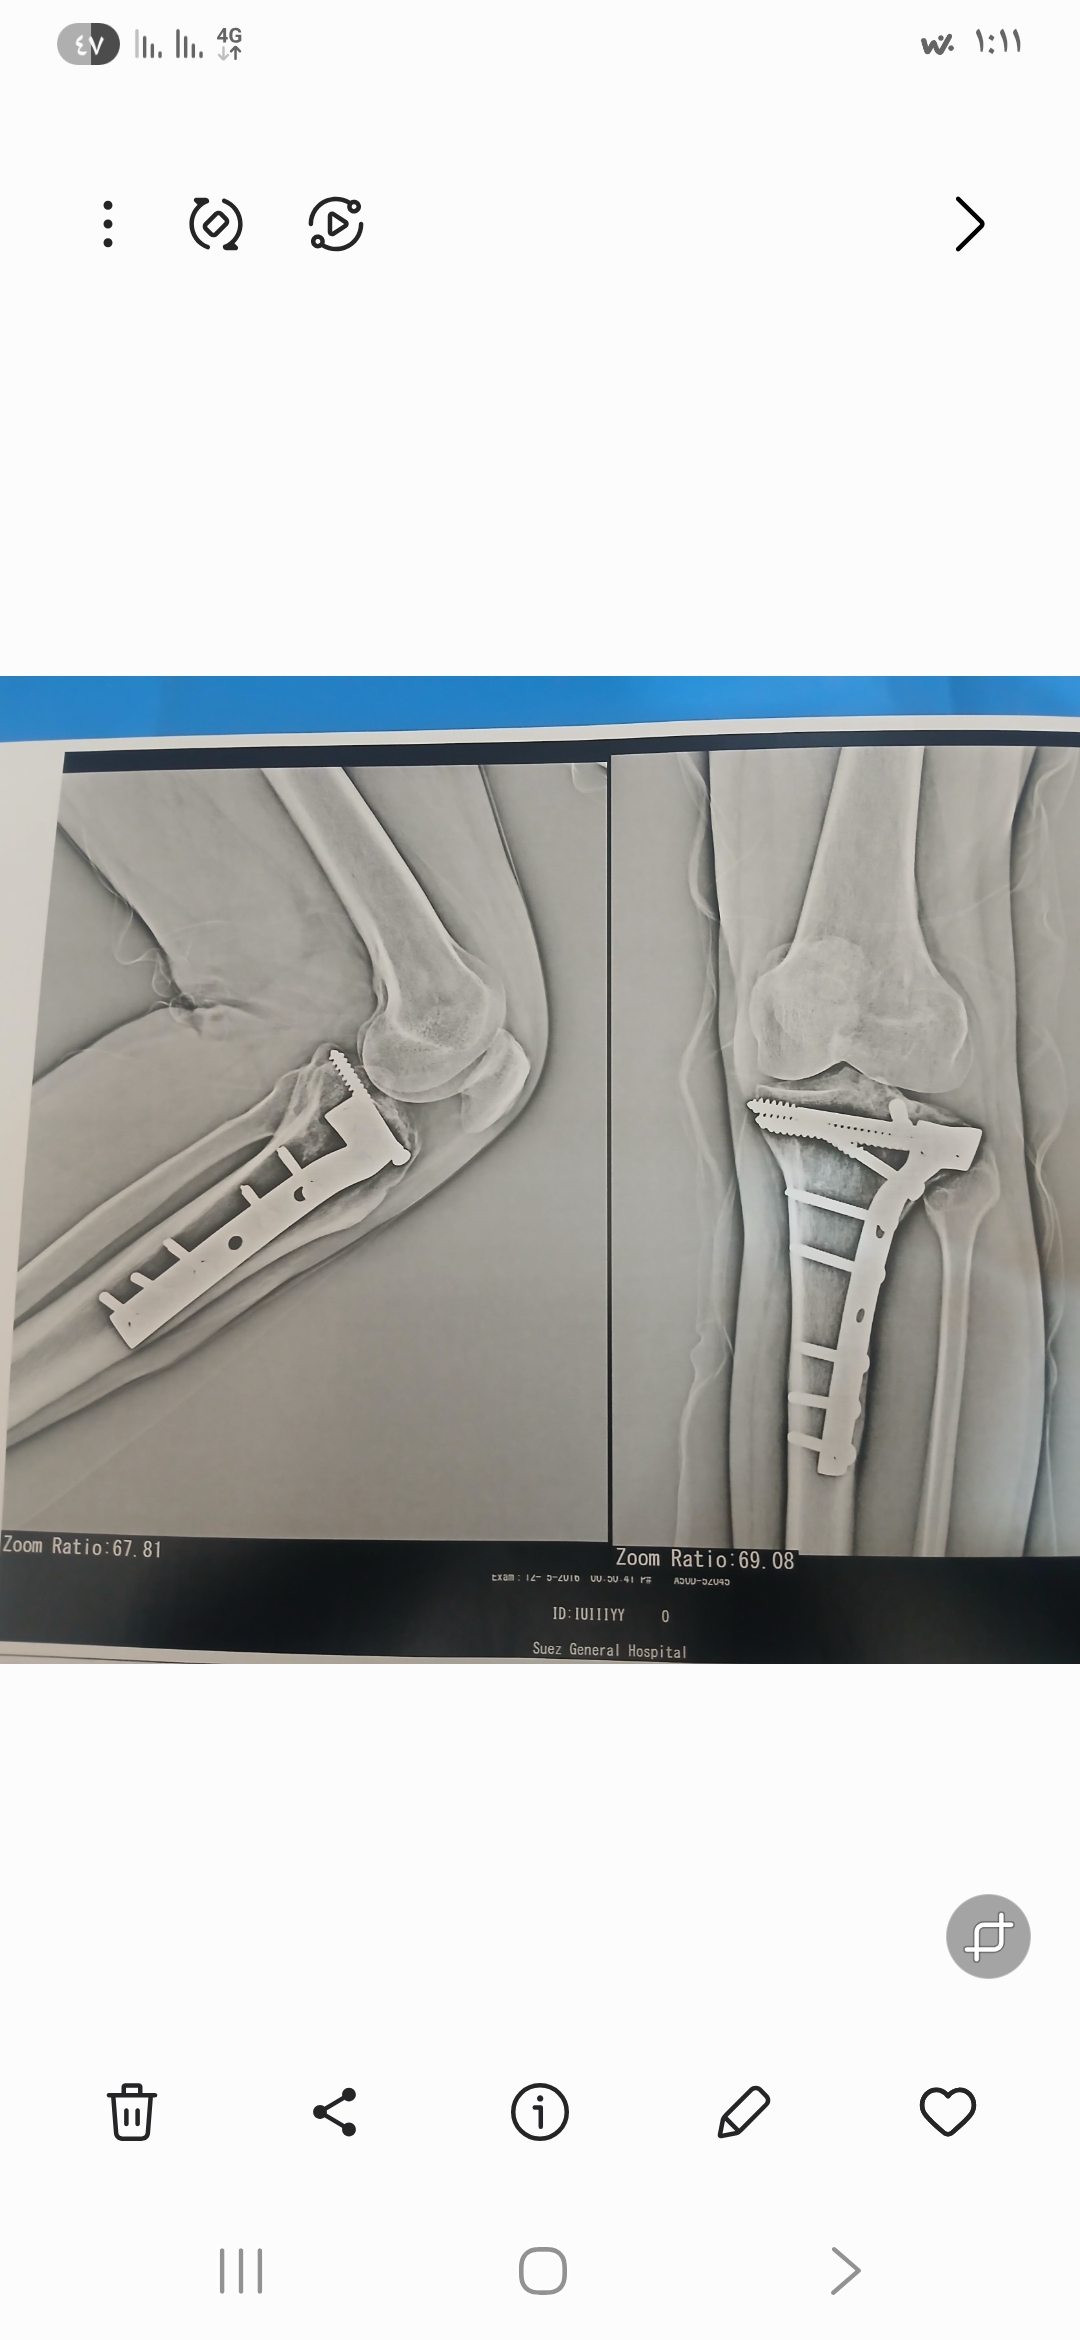

هل يوجد فرق بين صورتي الأشعة؟

كنت عاوز اعرف من دكتور عظام وأشعة في فرق بين الصورتين دي الاشعه قديمه وجديده مع بعض.

دي صورتين القديمه والجديده